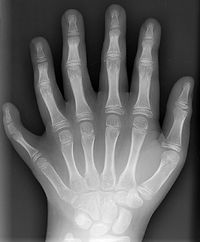

Šest prstů na jedné končetině (ruce nebo noze) se vzácně vyskytuje u některých lidí, někdy i párově. Tato anomálie nebo sklon k ní mohou být dědičné. Šestý prst někdy bývá plně funkční.

Šestiprstost je jedním z případů polydaktylie (hyperdaktylie), která je považována za poruchu chromozomálního původu.